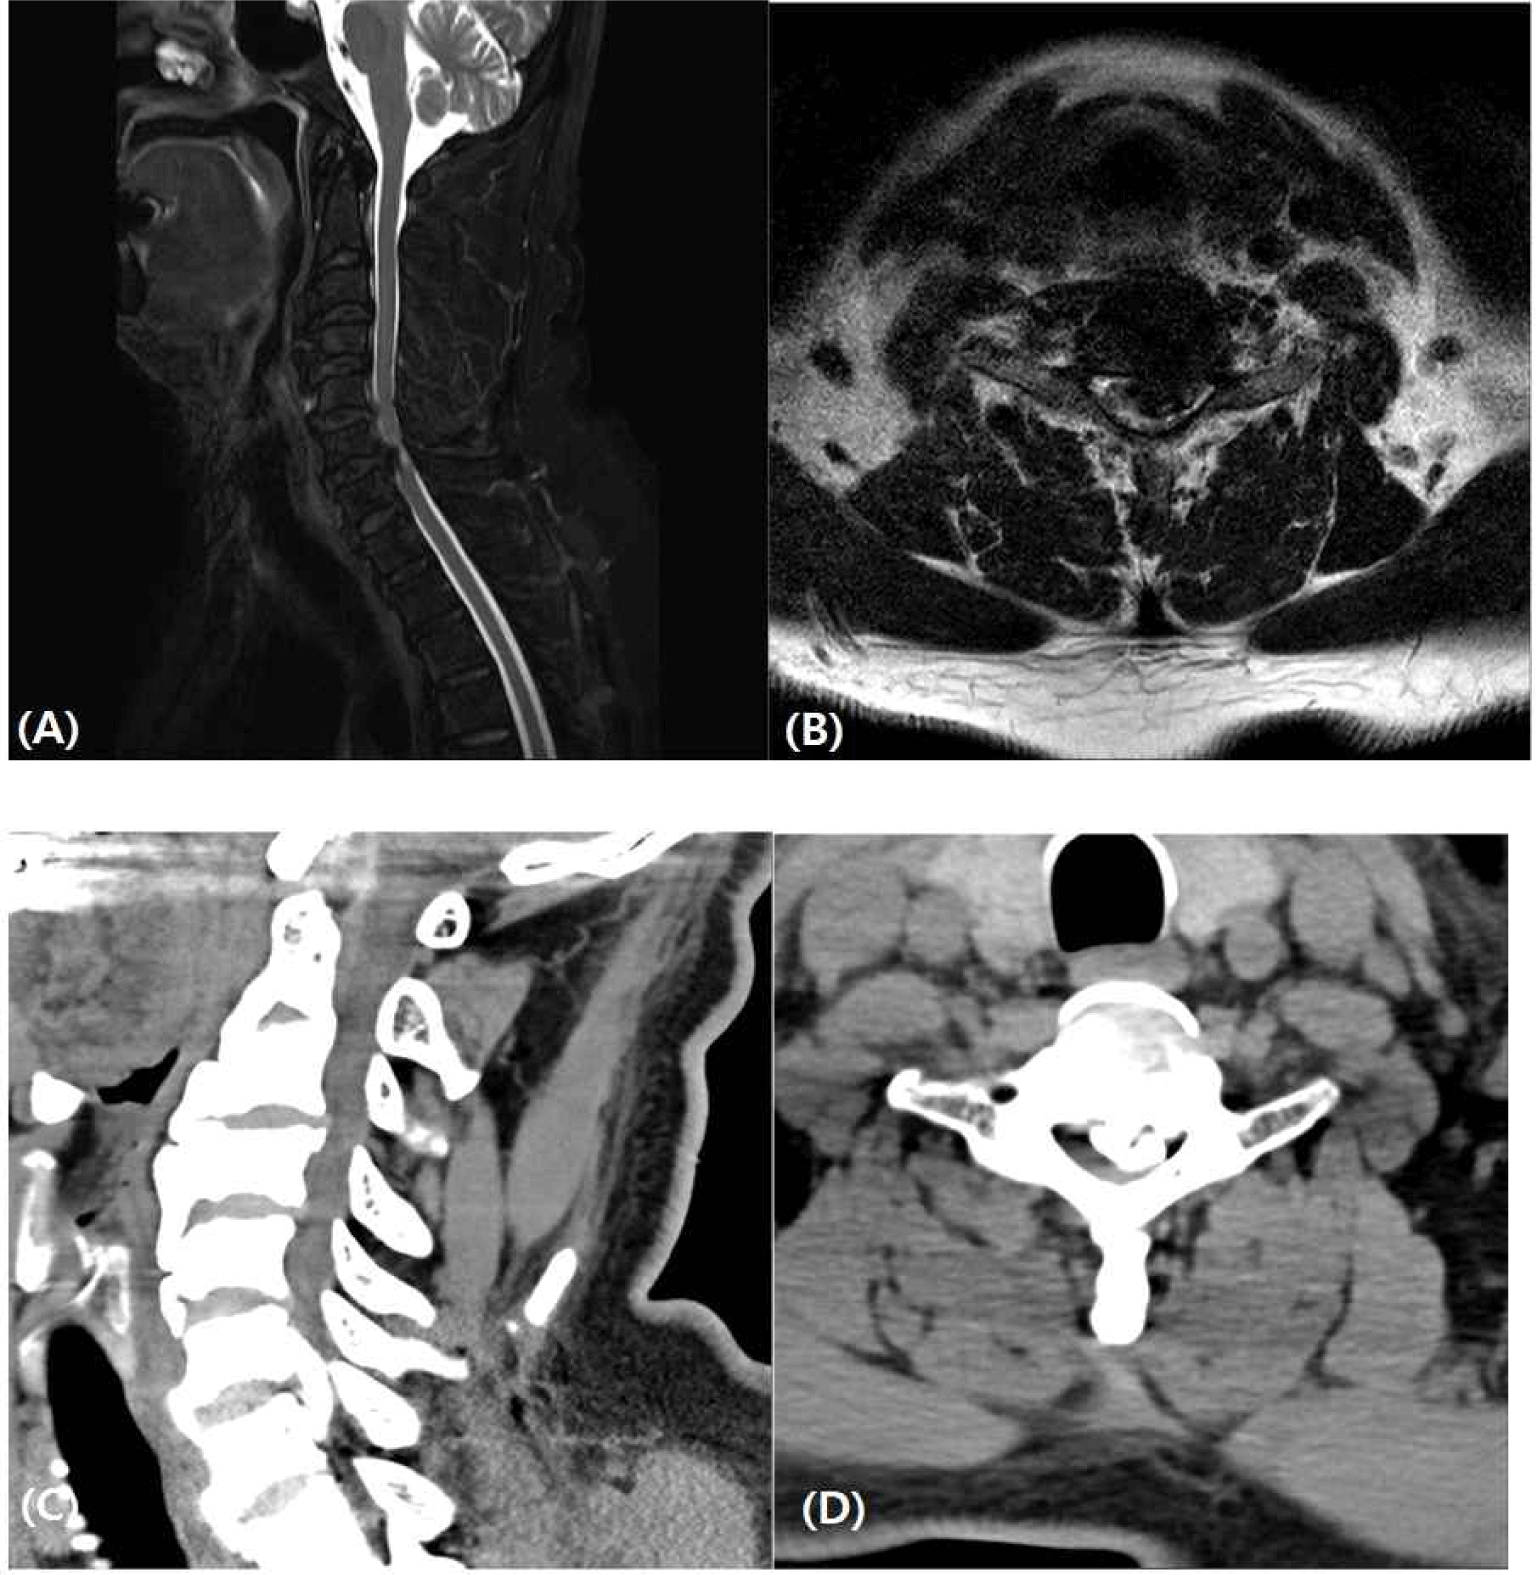

Intraoperative neurophysiologic monitoring in spinal cord cavernous angioma surgery: a case report

척수 해면상 혈관종 제거수술에서의 수술중 신경계 감시: 증례 보고

J Intraoper Neurophysiol 2023;5(1):17-23.